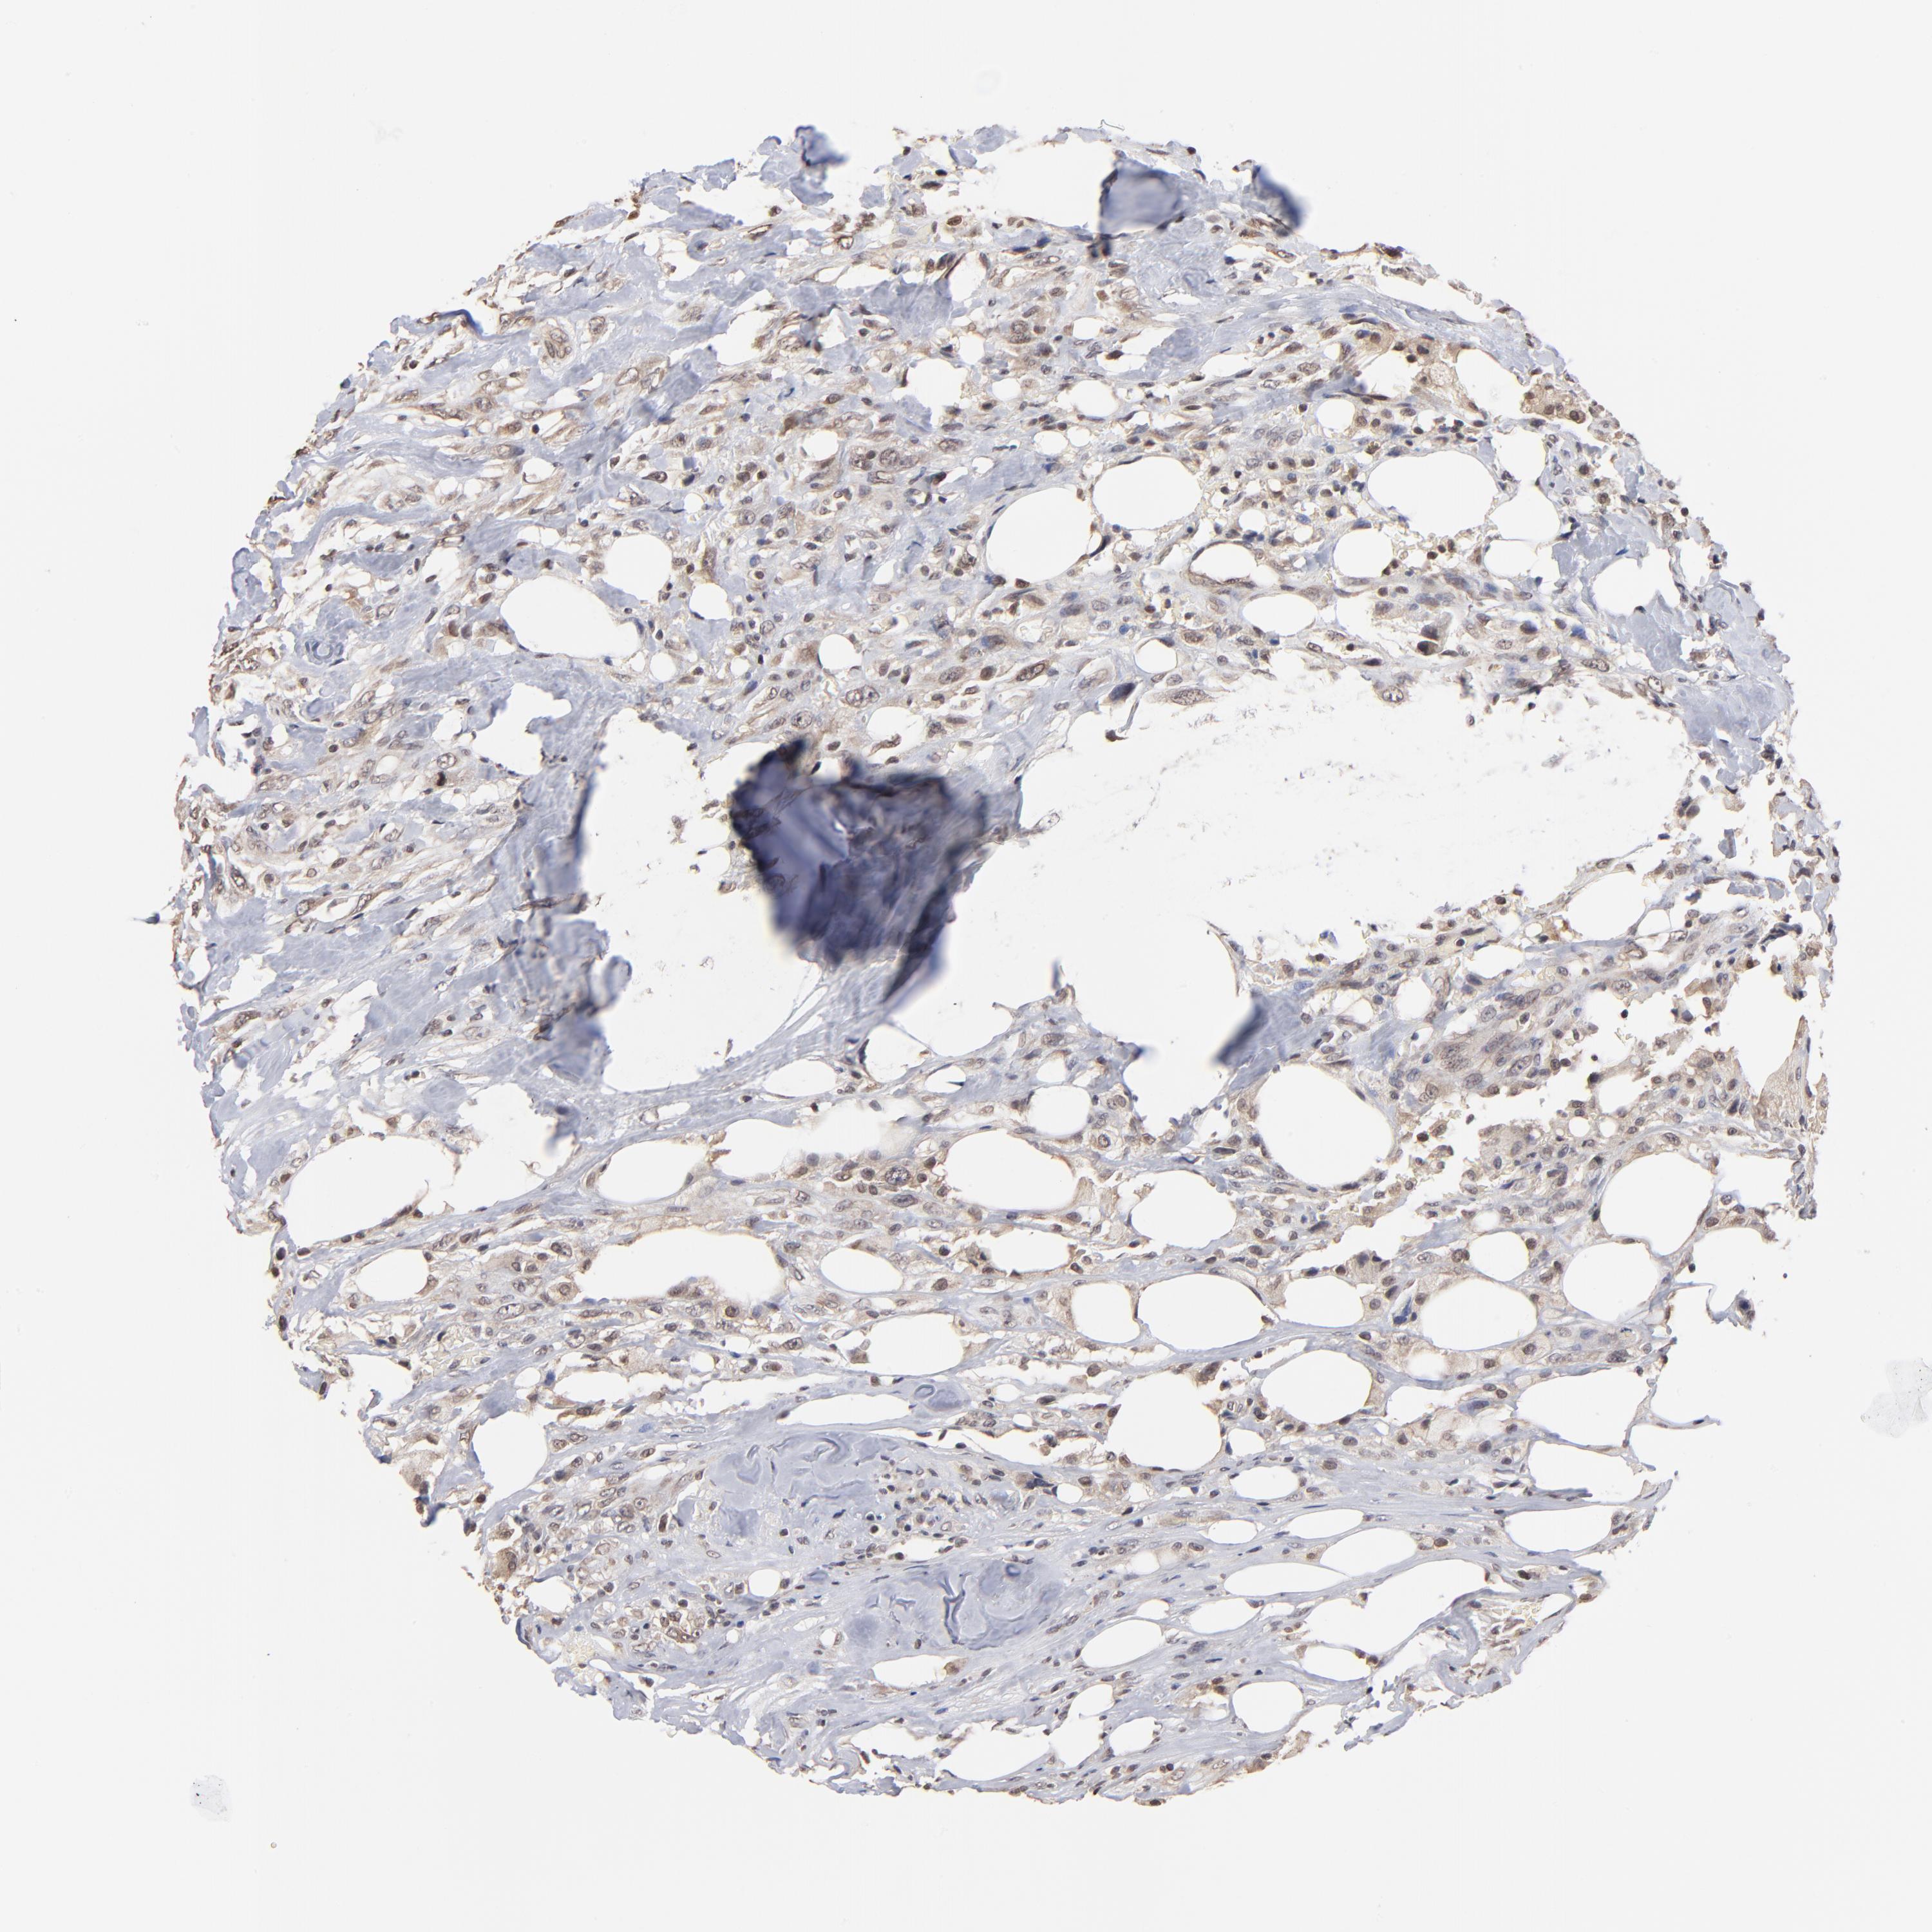

CANCER BREAST CANCER Show tissue menu

BRCA TCGA BRCA VALIDATION PROTEIN EXPRESSION

Breast cancer

Human cancer